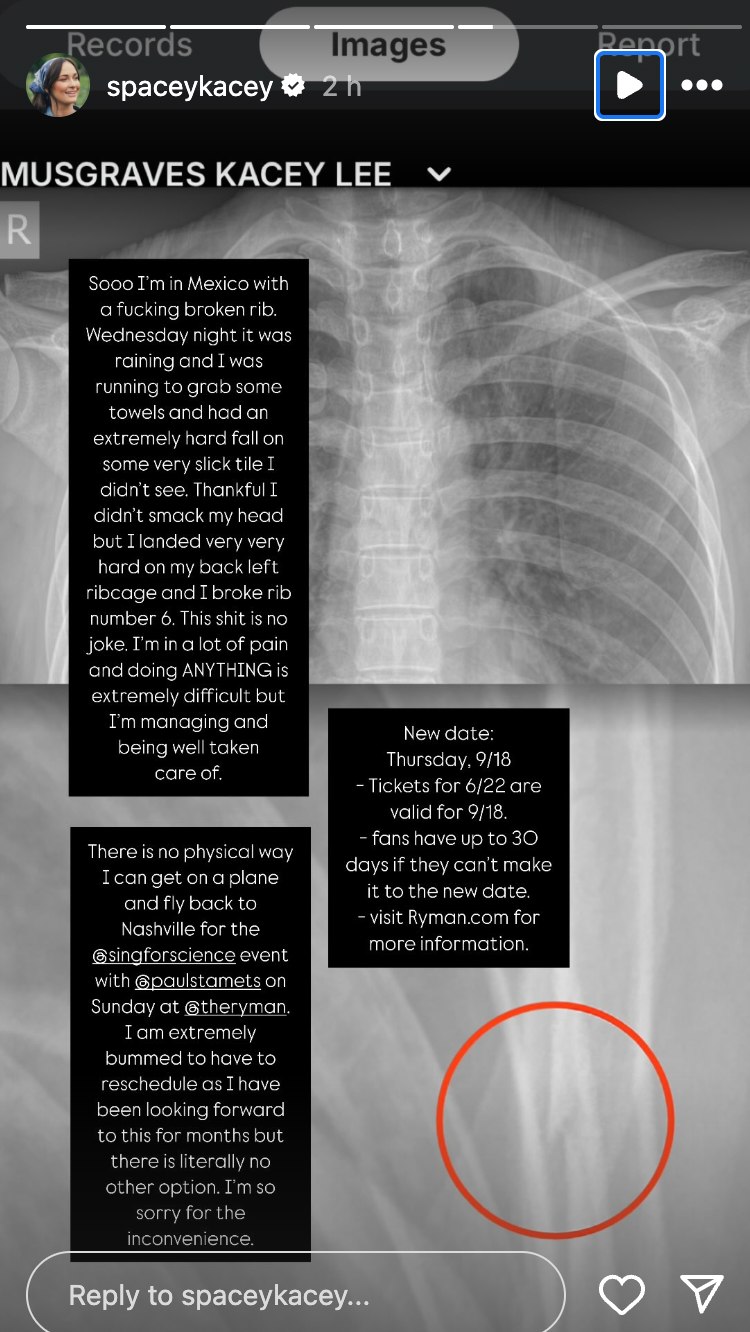

Posting X-ray images of her injury on her Instagram Story on Friday, Musgraves wrote: “Sooo I’m in Mexico with a f***ing broken rib. Wednesday night it was raining and I was running to grab some towels and had an extremely hard fall on some very slick tile I didn’t see.

“Thankful I didn’t smack my head but I landed very very hard on my back left ribcage and I broke rib number 6,” she revealed. “This s*** is no joke. I’m in a lot of pain and doing ANYTHING is extremely difficult but I’m managing and being well taken care of.”